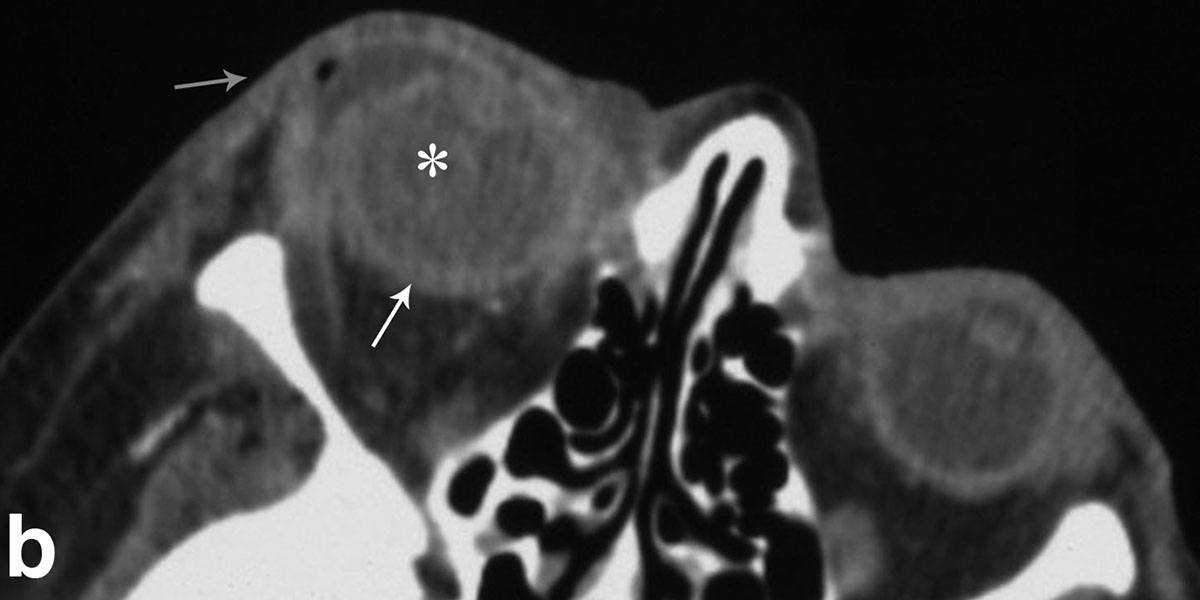

Generation of a new animal model for human acute angle-closure glaucoma